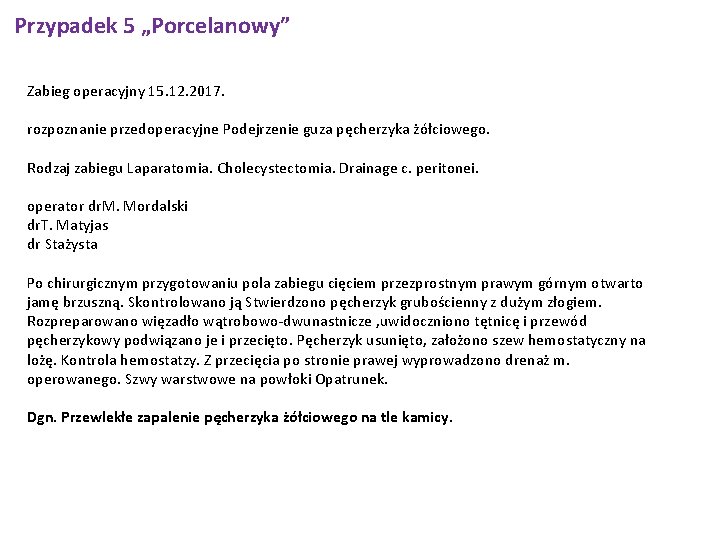

Przypadek 5 „Porcelanowy” Zabieg operacyjny 15. 12. 2017. rozpoznanie przedoperacyjne Podejrzenie guza pęcherzyka żółciowego. Rodzaj zabiegu Laparatomia. Cholecystectomia. Drainage c. peritonei. operator dr. M. Mordalski dr. T. Matyjas dr Stażysta Po chirurgicznym przygotowaniu pola zabiegu cięciem przezprostnym prawym górnym otwarto jamę brzuszną. Skontrolowano ją Stwierdzono pęcherzyk grubościenny z dużym złogiem. Rozpreparowano więzadło wątrobowo-dwunastnicze , uwidoczniono tętnicę i przewód pęcherzykowy podwiązano je i przecięto. Pęcherzyk usunięto, założono szew hemostatyczny na lożę. Kontrola hemostatzy. Z przecięcia po stronie prawej wyprowadzono drenaż m. operowanego. Szwy warstwowe na powłoki Opatrunek. Dgn. Przewlekłe zapalenie pęcherzyka żółciowego na tle kamicy.